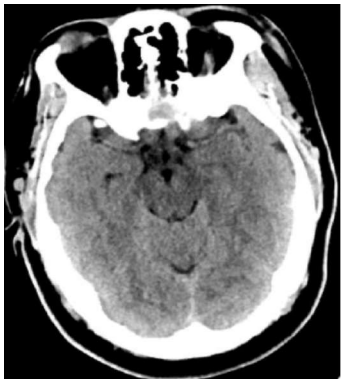

Uma mulher de quarenta anos de idade, obesa, hipertensa e tabagista, em uso irregular de hidroclorotiazida e anticoncepcional oral, compareceu ao pronto-socorro, queixando-se de cefaleia súbita de forte intensidade, iniciada há cerca de 12 h e associada a episódio de vômito. Refere que apresentou episódios semelhantes nas últimas duas semanas, de menor intensidade. Realizou a tomografia de crânio mostrada a seguir.

Com base nesse caso hipotético, assinale a alternativa que apresenta a conduta a ser adotada inicialmente.